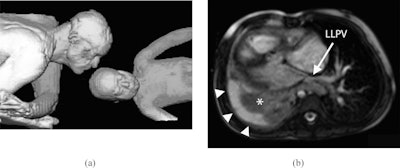

In one case highlighted in the series, the authors used the technique in a 2.5-year-old girl born with several heart defects. The girl had undergone biventricular repair and developed right lower and middle pulmonary vein stenosis and presented with recurrent pneumonia and chronic right pleural effusion.

The girl underwent cardiac MRI together with her father. All images were acquired during free breathing, and pauses in scanning were minimized to shorten scan time and allow the patient to focus her attention away from the test itself, the authors explained.

The examination revealed mild narrowing of the patient's left lower pulmonary vein and of the distal right ventricle to pulmonary artery conduit. Both ventricles were dilated with reduced ejection fractions. There was collapse/consolidation of the patient's right lung and a large right pleural effusion.